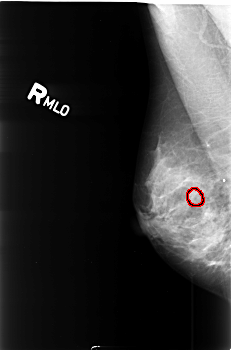

Digital Database for Screening Mammography

Volume: benign_06 Case: B-3419-1

B_3419_1.RIGHT_MLO

RIGHT_MLO LINES 4544 PIXELS_PER_LINE 3000 BITS_PER_PIXEL 12 RESOLUTION 50 OVERLAY

FILE: B_3419_1.RIGHT_MLO.OVERLAY

TOTAL_ABNORMALITIES 1

ABNORMALITY 1

LESION_TYPE CALCIFICATION TYPE PLEOMORPHIC DISTRIBUTION CLUSTERED

ASSESSMENT 4

SUBTLETY 2

PATHOLOGY BENIGN

TOTAL_OUTLINES 1